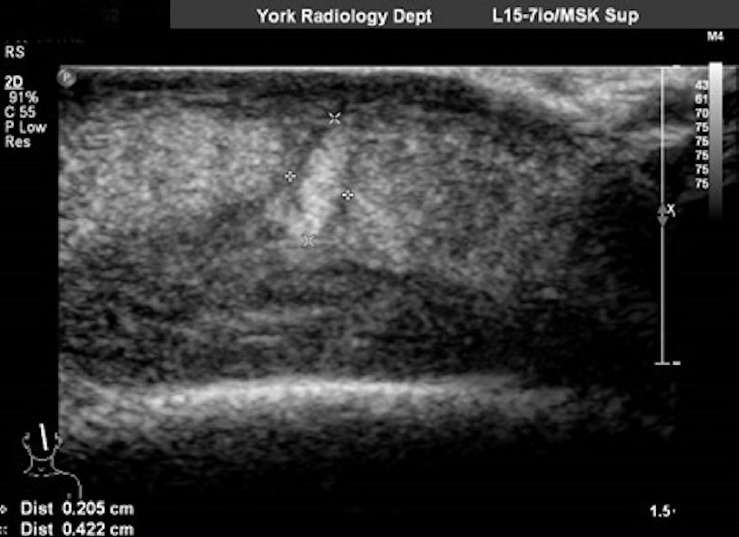

Contudo, como a mulher desenvolveu uma forte dor de cabeça constante, o inchaço começou a se espalhar para o rosto e os olhos, e a lesão na testa começou a vazar (sim, a coisa só piora...), lá foi ela ao hospital. Uma vez na emergência, os médicos constataram que o inchaço na testa era resultado de uma larva alojada no local, e a criatura foi removida com a aplicação de vaselina na área.

Entretanto, depois de submeter a paciente a mais exames – para garantir que sua testa não abrigava mais “surpresas” –, os médicos descobriram outra larvinha sorrateira e tiveram que realizar uma pequena cirurgia para removê-la dali. Os bichinhos foram encaminhados para reconhecimento e identificados como sendo da espécie Cordylobia rodhaini, filhotinhos de um inseto conhecido como mosca-de-Lund e que pode ser encontrado nas florestas tropicais da África.